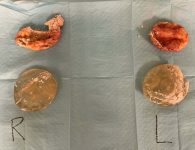

At surgery, Dr. Lyle found calcified capsules and removed them in their entirety. Inside were discovered ruptured silicone gel dual-chambered breast implants that were about 250 cc and had heavy calcification within the capsule. Because of the severity of the encapsulation, a site change was done, placing the implants under the pectoral muscle and using xenograft – called Strattice – that has been shown to reduce recurrent capsular contracture. This product is derived from pigskin, but all of the cells and antigens have been removed, and this is used in cosmetic and reconstructive procedures. She had 330 cc moderate plus Sientra silicone gel breast implants placed. She did require drain tubes, which were removed in 1 week.